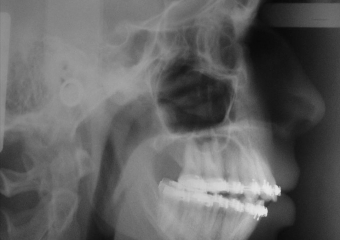

Telerradiografia inicial

Telerradiografia final